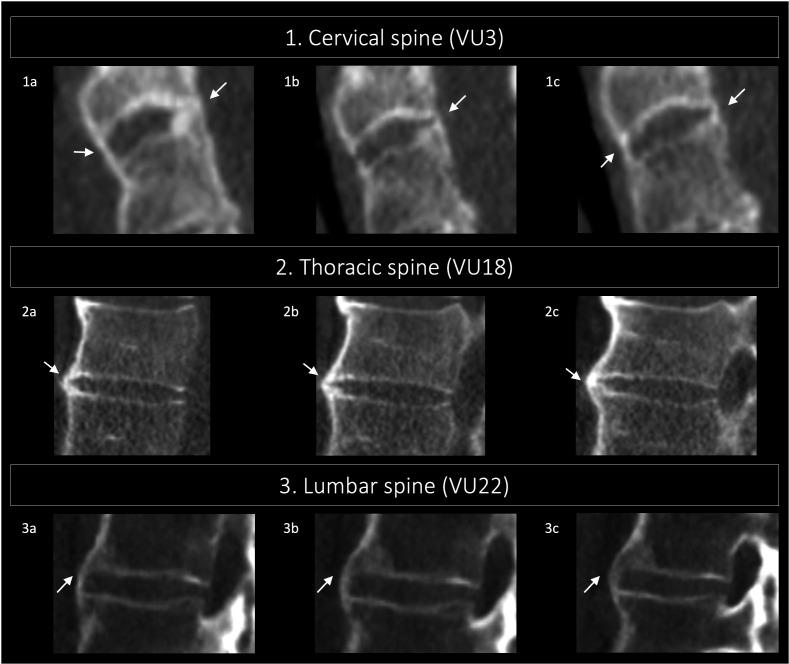

In this paper, illustrations of the different grades and views of the CTSS are presented. CTSS is used to measure bone formation in the spine of patients with axial spondyloarthritis (axSpA), in the form of syndesmophytes. In both the sagittal and coronal planes, syndesmophytes can be graded from 0 to 3 over 23 vertebral units starting at C2 and ending at S1. The CTSS ranges from 0 (absence of axSpA-related syndesmophytes) to 552 (total ankylosis of the spine).

The current atlas contains low-dose CT images of the spine without lesions (for reference) and all grades of syndesmophytes in different planes used in the CTSS. Examples are arranged per spinal segment (cervical, thoracic and lumbar).

本文展示了不同 CTSS 分级和视图的图像。CTSS 用于测量 axSpA 患者脊柱中的骨形成情况,以骨桥的形式表现。在矢状面和冠状面,从 C2 到 S1 的 23 个椎体单元上,骨桥可从 0 级到 3 级进行分级。CTSS 的范围从 0(无 axSpA 相关的骨桥)到 552(脊柱完全强直)。

目前的图谱包含无病变的脊柱低剂量 CT 图像(供参考),以及 CTSS 中不同平面的所有骨桥分级。示例按脊柱节段(颈椎、胸椎和腰椎)排列。